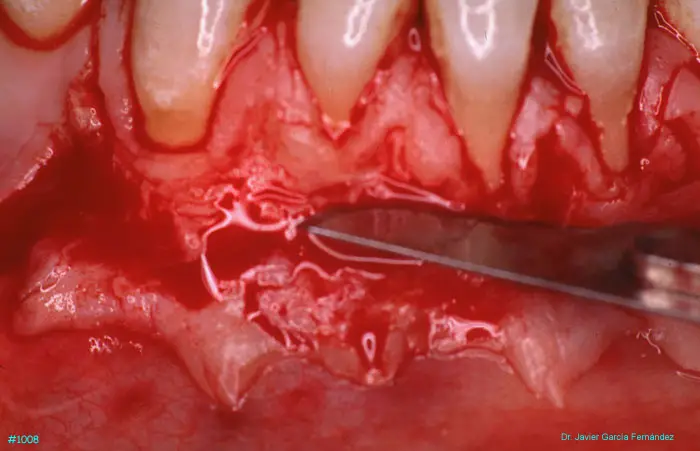

Atlas of Surgical Techniques in Periodontics. Chapter III. Atlas de Técnicas Quirúrgicas en Periodoncia